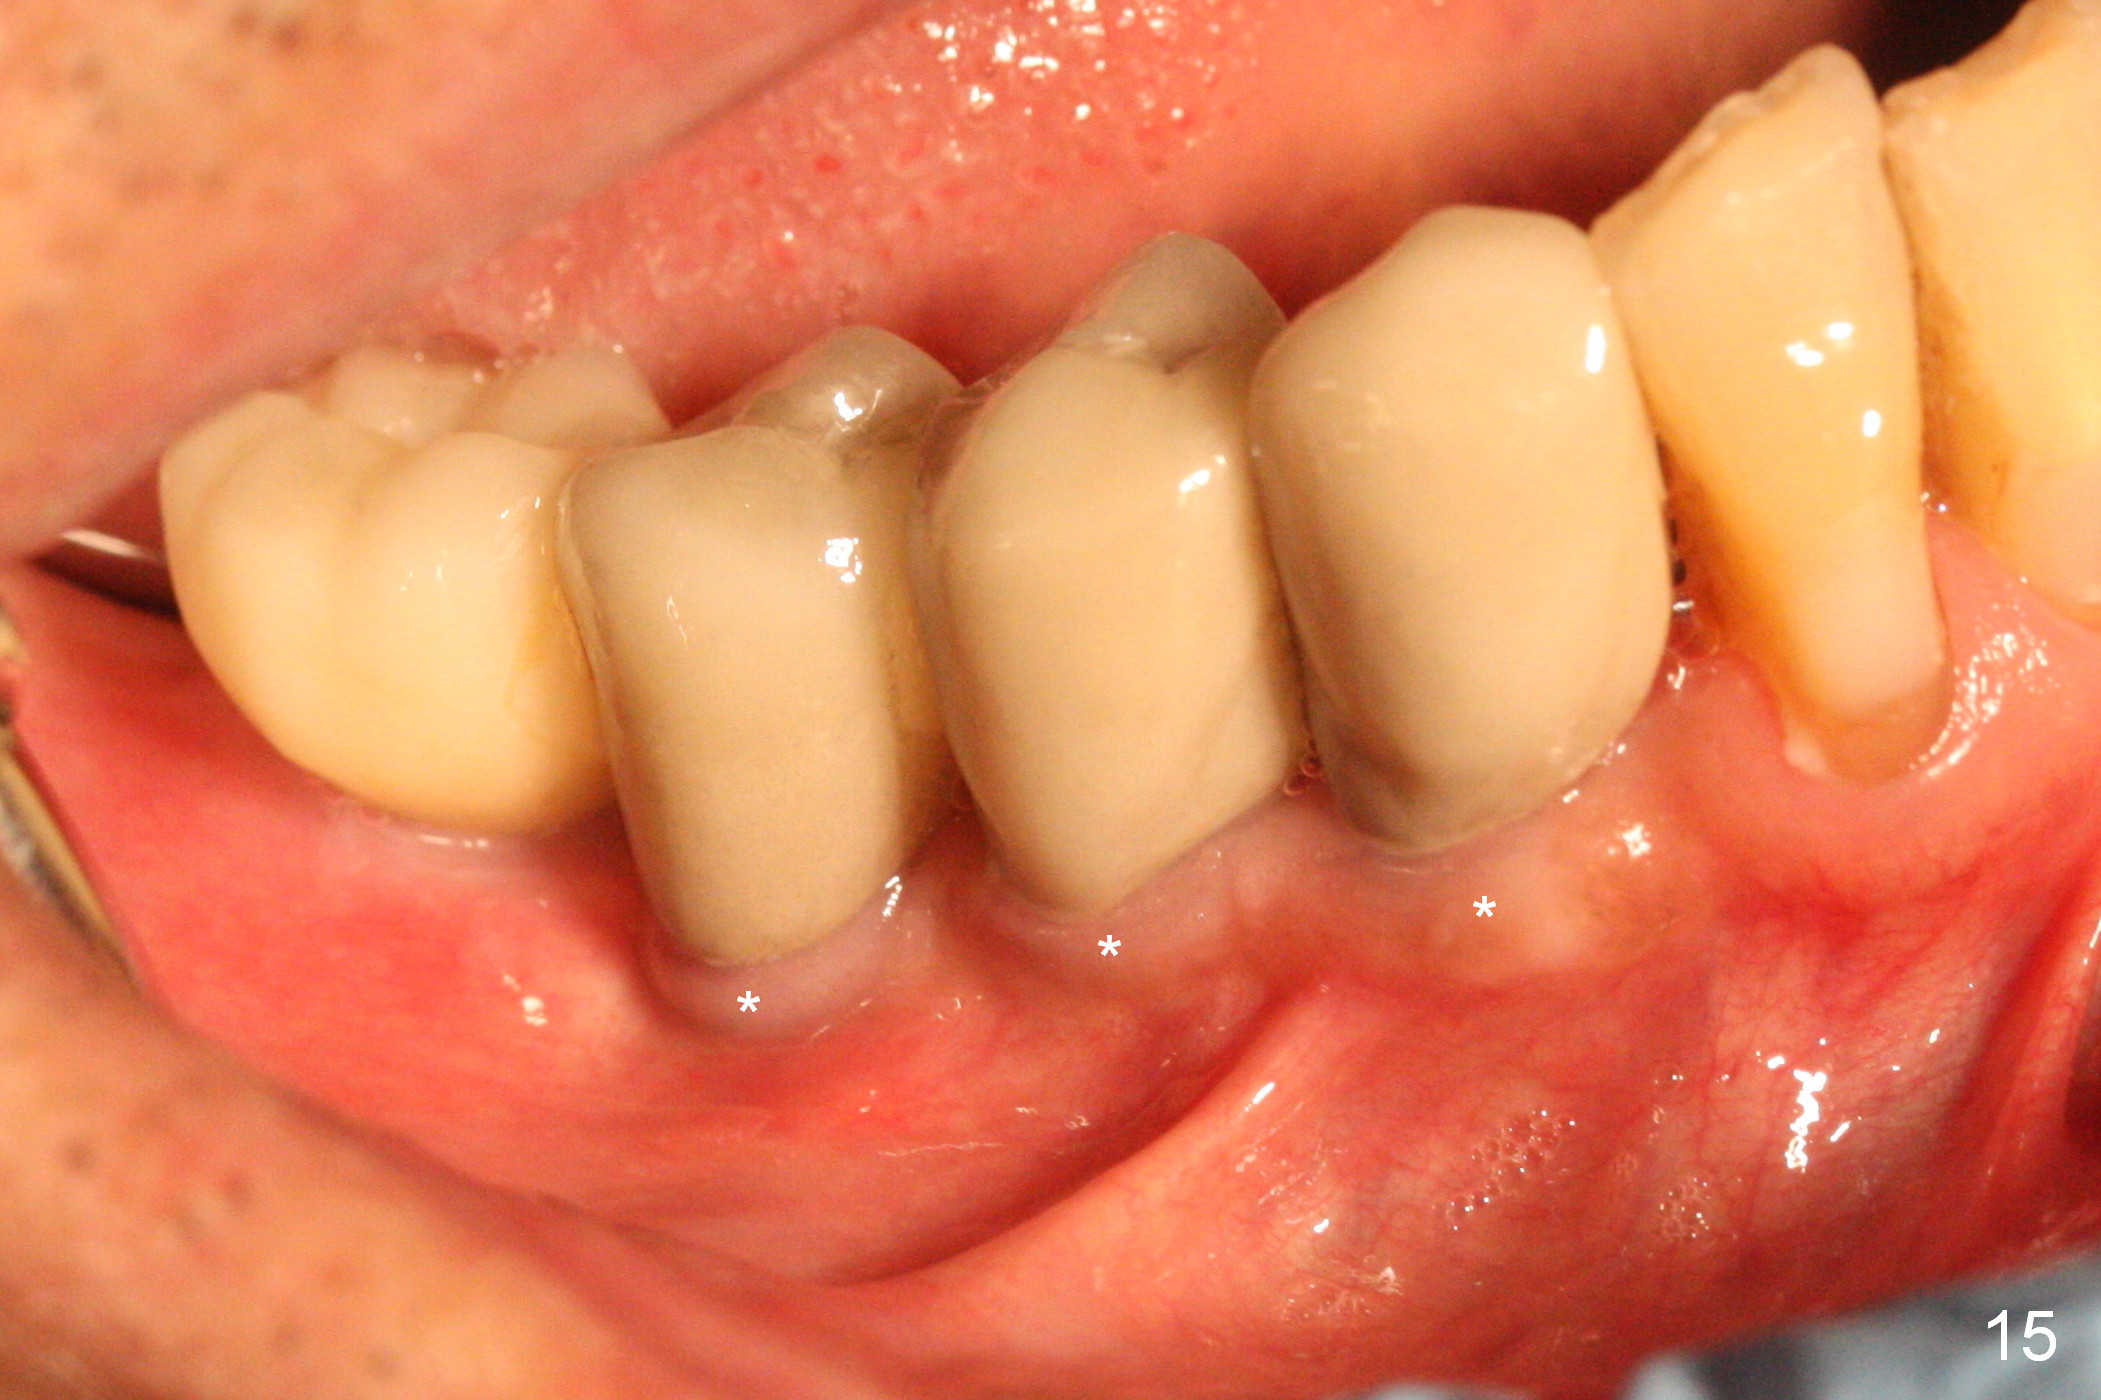

There appears to be no bone loss 2 years 5 months post cementation (Fig.14).  Gingival bands form around the implants at #27-29 three years 1 month post cementation (Fig.15 *).